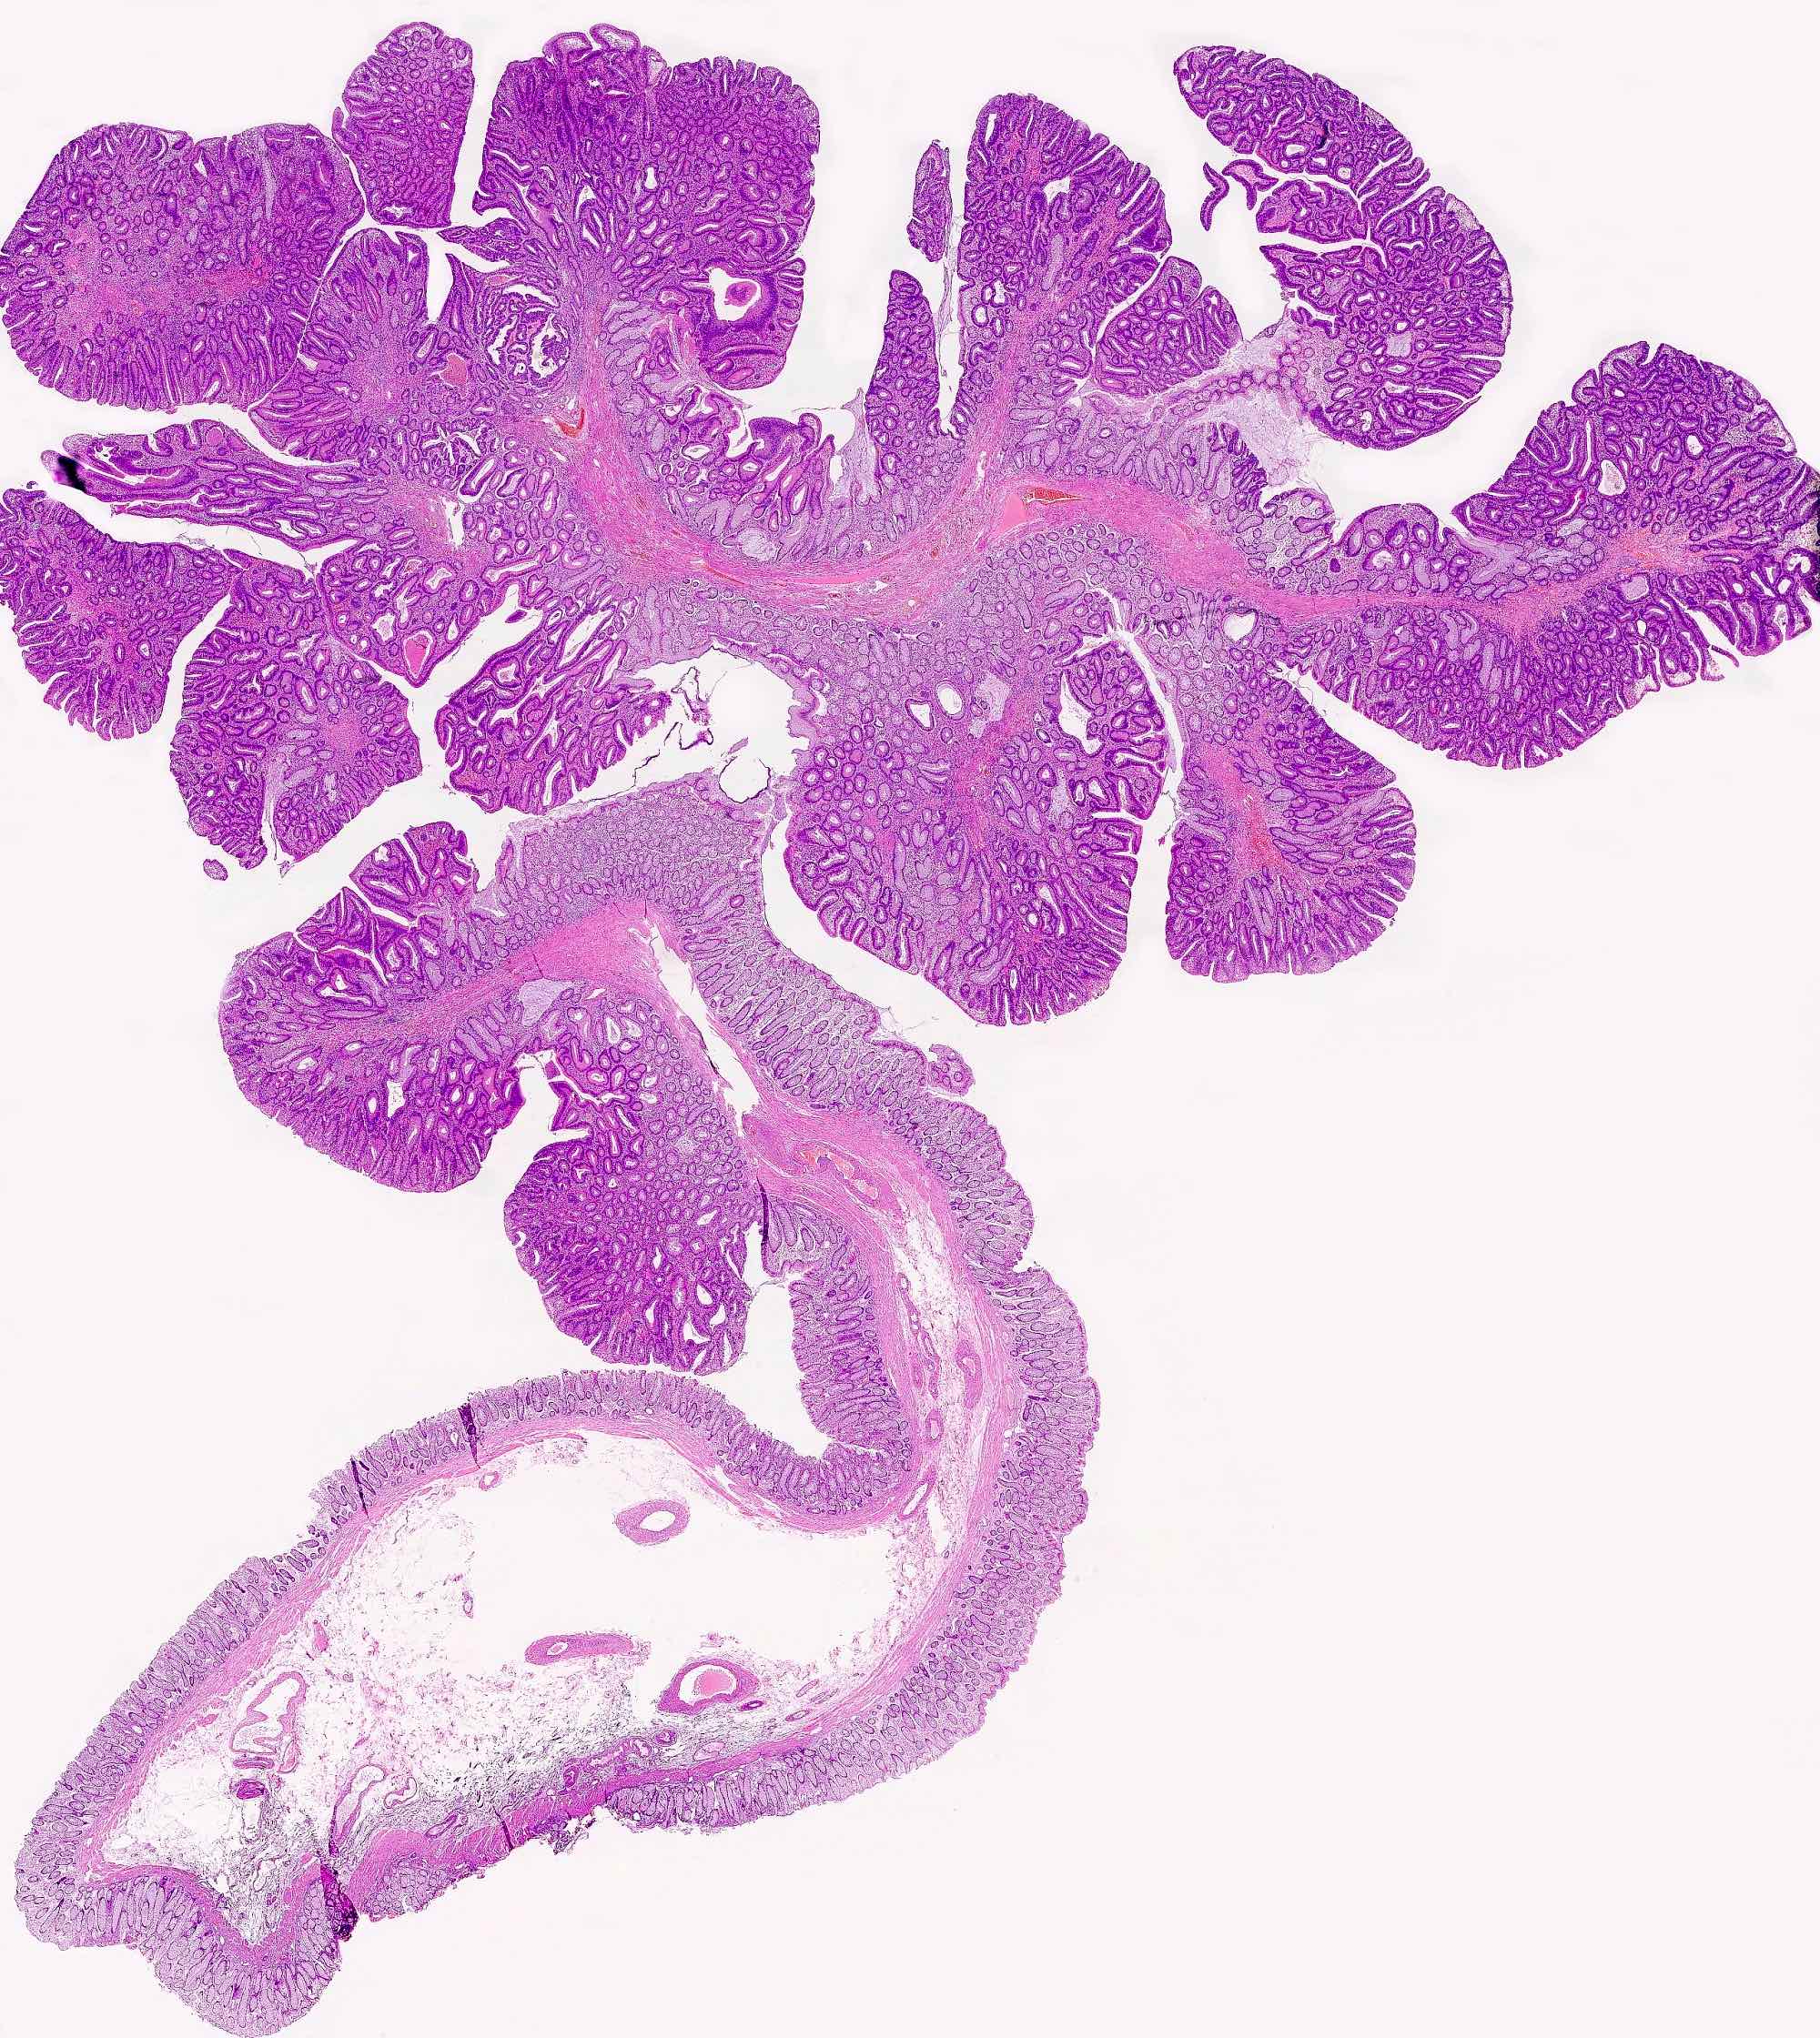

Microscopic (histologic) description

- Polypoid colonic mucosa covered with dysplastic epithelium comprised of hyperchromatic, elongated nuclei arranged in a pseudostratified manner

- Dysplasia is typically low grade but may also be high grade, with architectural (cribriforming, luminal necrosis) and cytologic changes (vesicular chromatin, nucleoli, loss of basal polarity)

- Abrupt transition from normal to dysplastic mucosa is commonly present

- Variable amounts of mucin loss

- Metaplasia may be present: osseous, squamous or Paneth cells (J Clin Pathol 2005;58:220, J Surg Oncol 1984;26:130)

- Pseudoinvasion can mimic progression to adenocarcinoma but displaced glands are benign and surrounded by lamina propria and often hemosiderin (Mod Pathol 2015;28:S88)

- May rarely show clear cell features (Am J Surg Pathol 2010;34:1344)

Microscopic (histologic) images

Contributed by Andrew L.J. Dunn, M.D. and Christopher Hartley, M.D.

Contributed by @Andrew_Fltv and @liverwei on Twitter